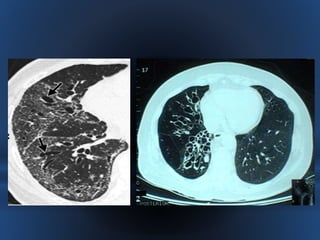

- El diagnóstico se confirma mediante la tomografía computarizada de alta

resolución (TACAR) torácica, que es la exploración con mayor sensibilidad

(96%) y especificidad (93%) en la detección de bronquiectasias y en la

valoración de su evolución.

TOMOGRAFIA COMPUTARIZADA DE ALTA RESOLUCION

= GOLD STANDARD

• DIAGNÓSTICO -Las bronquiectasias deben ser sospechadas en los pacientes con tos y expectoración persistentes, infecciones respiratorias recurrentes, hemoptisis recidivantes, infiltrados pulmonares crónicos o una radiografía de tórax sugestiva. - El diagnóstico se confirma mediante la tomografía computarizada de alta resolución (TACAR) torácica, que es la exploración con mayor sensibilidad (96%) y especificidad (93%) en la detección de bronquiectasias y en la valoración de su evolución.

TOMOGRAFIA COMPUTARIZADA DEALTA RESOLUCION = GOLD STANDARD